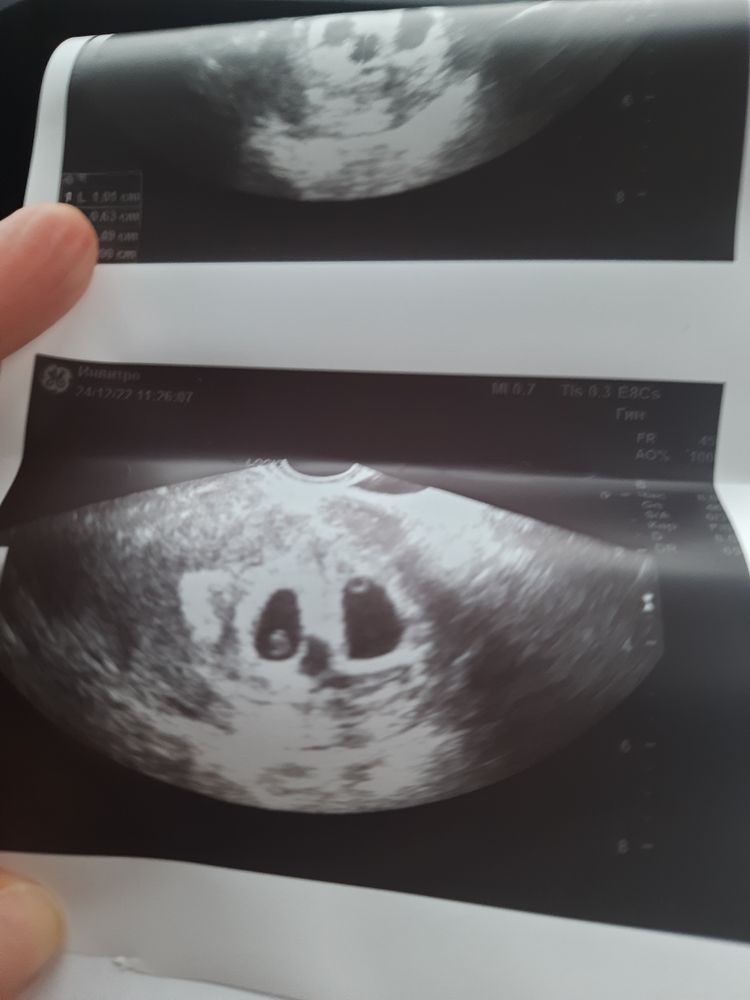

26дпп. Пронесло)

Бусинки ) у вас 2 подсаживали ?) размеры примерно одинаковые пя и ктр?)

Мария , их сегодня не замеряли, в понедельник спрошу у ре, можно ли) но мне кажется, что "вратарь" покрупнее) да, у нас двоих подсаживали, двое и прижились)))